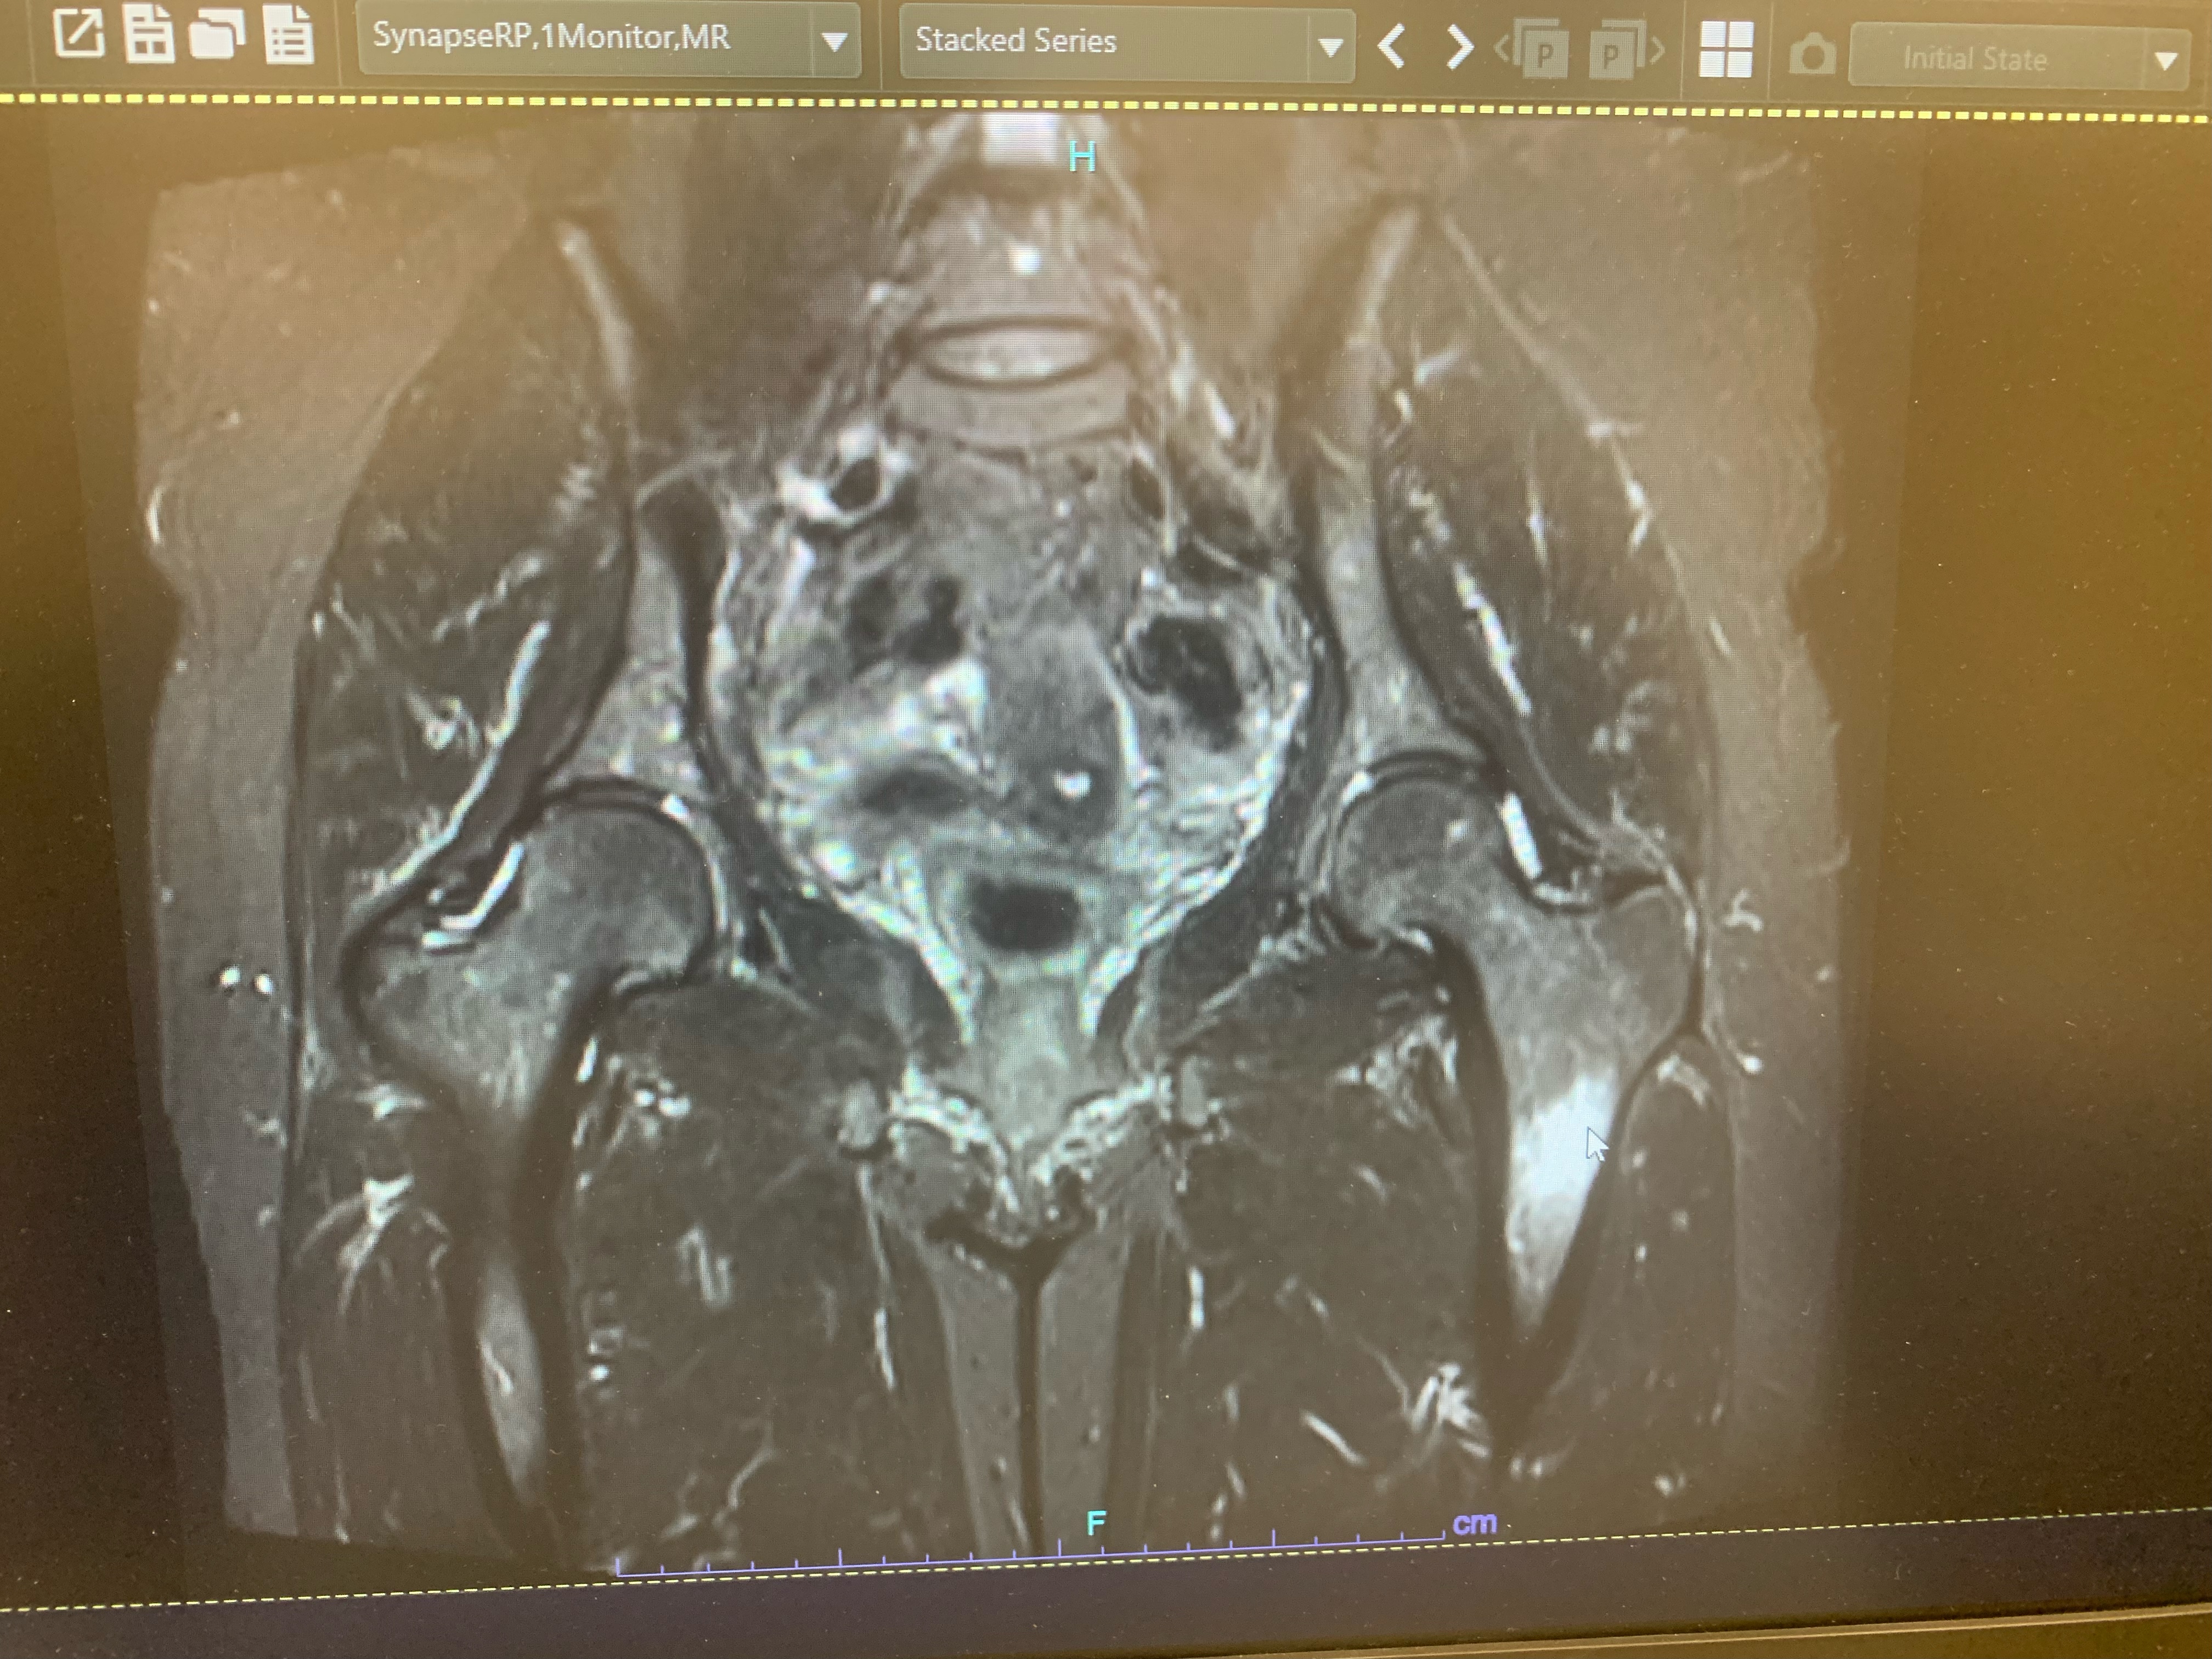

The MRI showed a Femoral stress fracture and the DXA-scan showed healthy bones. The first caused me to cancel my race, which was hard and still hurts as the start creeps closer. The second made me hopeful. So many running-critics, even those in my own family, are always warning of poor bone health. When my doctor had ordered a bone scan I was scared. What if I proved all the critics right? What if my bones were paper-thin and all about to break at any moment? Thankfully, that was not the case and my bones were strong. I had gone through three years of running thousands of miles on all kinds of trails and conditions without an injury that instead of being sad, part of me knew how lucky I had been. “I don’t like to call them over-use injuries,” my sports doc aid. “Because it implies, you’re doing something wrong. You’re not doing anything wrong; you’re just using your body to do what you love.”